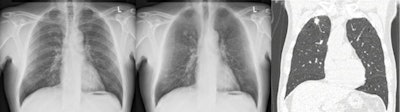

Example case in which the radiologists improved their detection of a 13 mm, pathologically proven, squamous cell carcinoma in the right upper lobe.

Example case in which the radiologists improved their detection of a 13 mm, pathologically proven, squamous cell carcinoma in the right upper lobe.The five radiologists had between three and 17 years' experience, and they were accompanied by one second-year and two third-year trainees. The readers evaluated 300 study cases in different randomized orders. Before the reading sessions, they evaluated a training set of 40 cases with and without BSI. During this training session, the researcher gave instantaneous feedback to the observers. None of the observers had previous experience in reading CXR with BSI, or dual energy chest radiography. Readings were carried out using a 30-inch (Flexscan SW3031W, Eizo) DICOM-calibrated LCD monitor in a darkened room, the authors wrote.